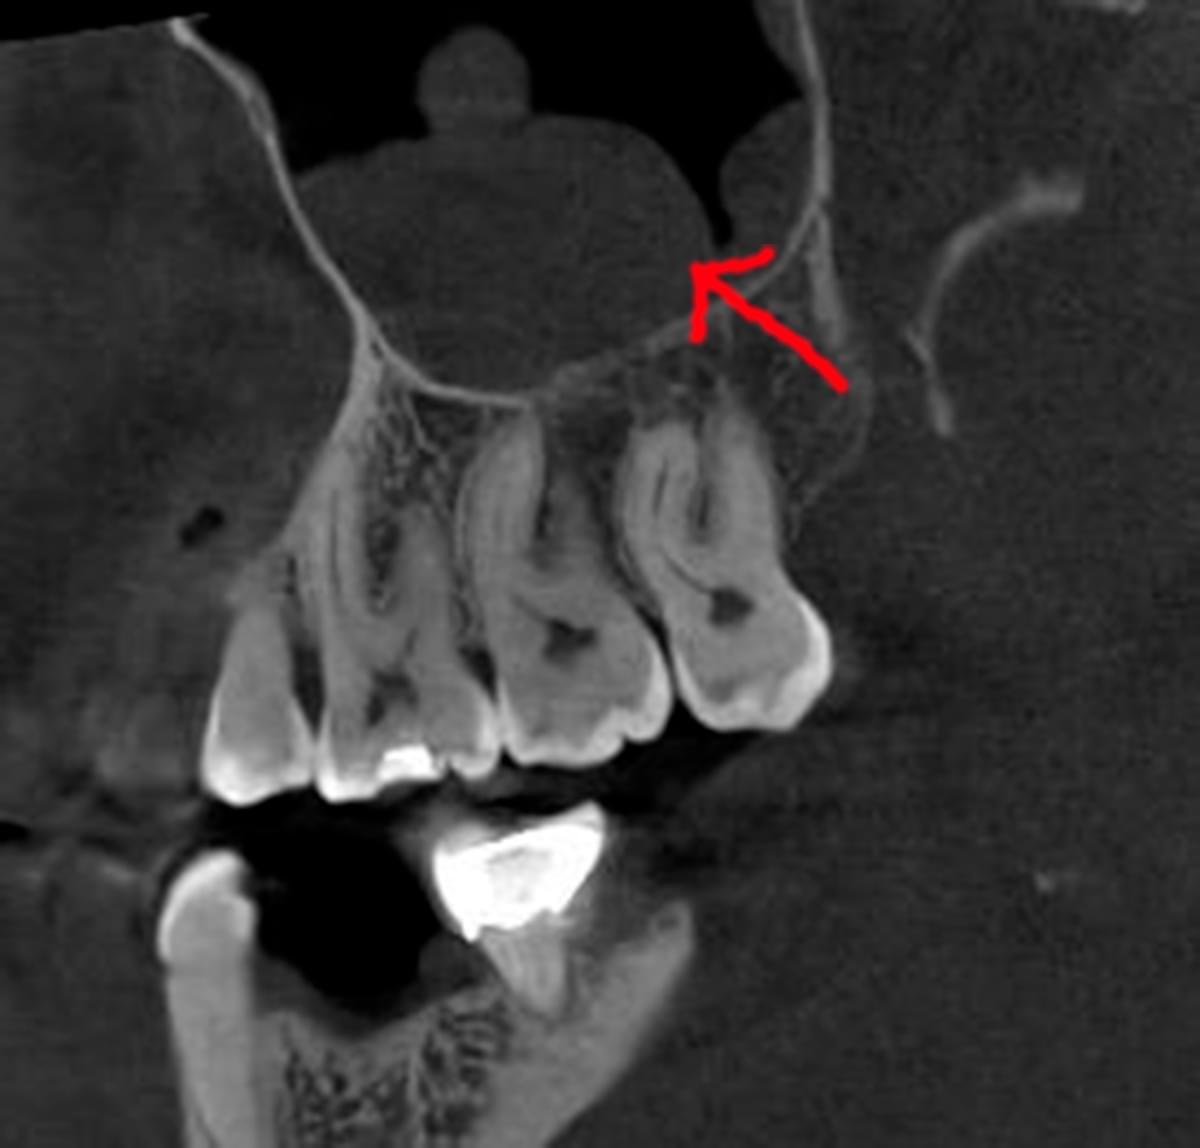

Коли коріння «ховає сюрпризи» - Корені зубів часто мають складну кривизну, гачкоподібні закручення або розгалуження, які на звичайному 2D-знімку накладаються один на одного, створюючи ілюзію прямого каналу. На плоскій картинці неможливо побачити реальний об'єм та напрямок вигину, що критично важливо при видаленні «зубів мудрості» або ендодонтичному лікуванні. КТ MyRay дає змогу лікарю заздалегідь побачити 3D-геометрію кожного кореня, оцінити його близькість до нижньощелепного нерва чи гайморової пазухи та підібрати правильну тактику роботи. Це мінімізує ризики поломки інструменту в каналі або травмування сусідніх структур, перетворюючи складну хірургію на прогнозовану процедуру.